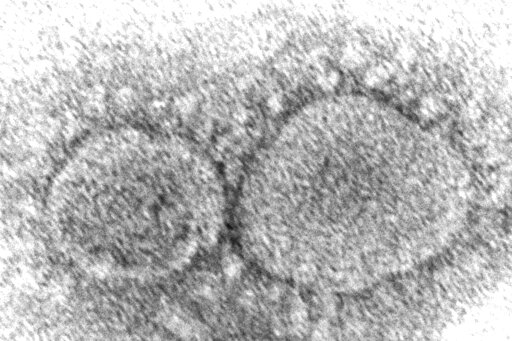

The coronavirus mutant that is now dominant in the United States is a member of the omicron family but scientists say it spreads faster than its omicron predecessors, is adept at escaping immunity and might possibly cause more serious disease.

The omicron “subvariant” gaining ground in the U.S. — known as BA.2.12.1 and responsible for 58% of U.S. COVID-19 cases last week — isn't the only one affected by the delta mutation. The genetic change is also present in the omicron relatives that together dominate in South Africa, known as BA.4 and BA.5. Those have exactly the same mutation as delta, while BA.2.12.1 has one that's nearly identical.